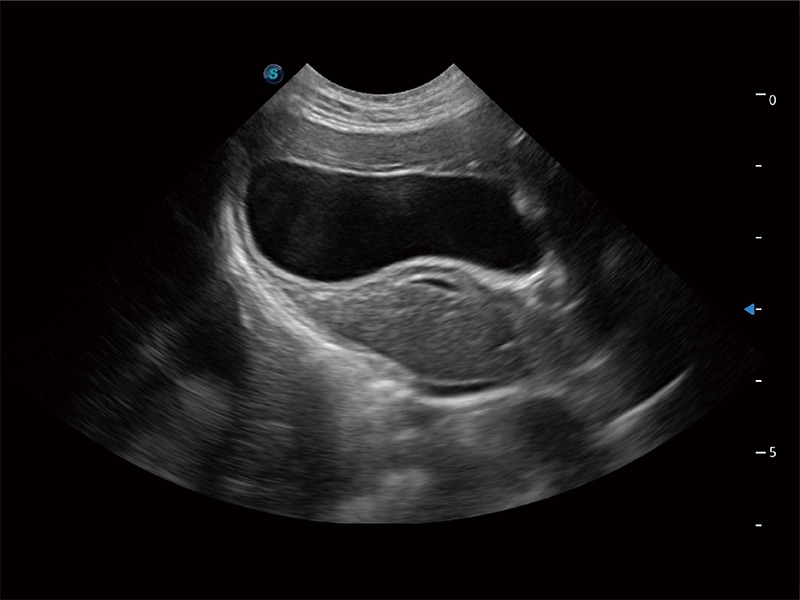

一鍵自動(dòng)識(shí)別膀胱壁及自動(dòng)測(cè)量膀胱容積,不受膀胱形狀和大小的限制,幫助醫(yī)生快速精準(zhǔn)獲得測(cè)量的數(shù)據(jù)。